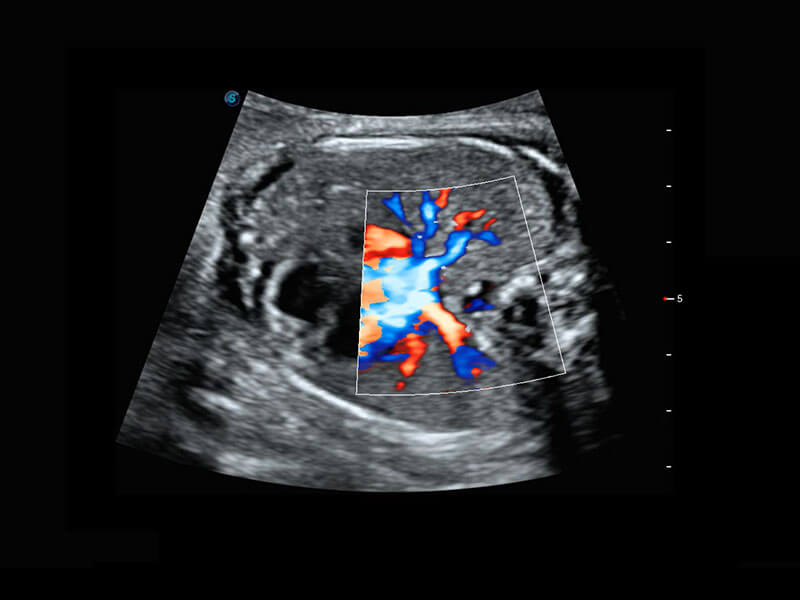

• 四腔切面

• 四腔心血流

P60搭载一系列胎儿心脏成像技术,实现精细的胎儿心脏评估。